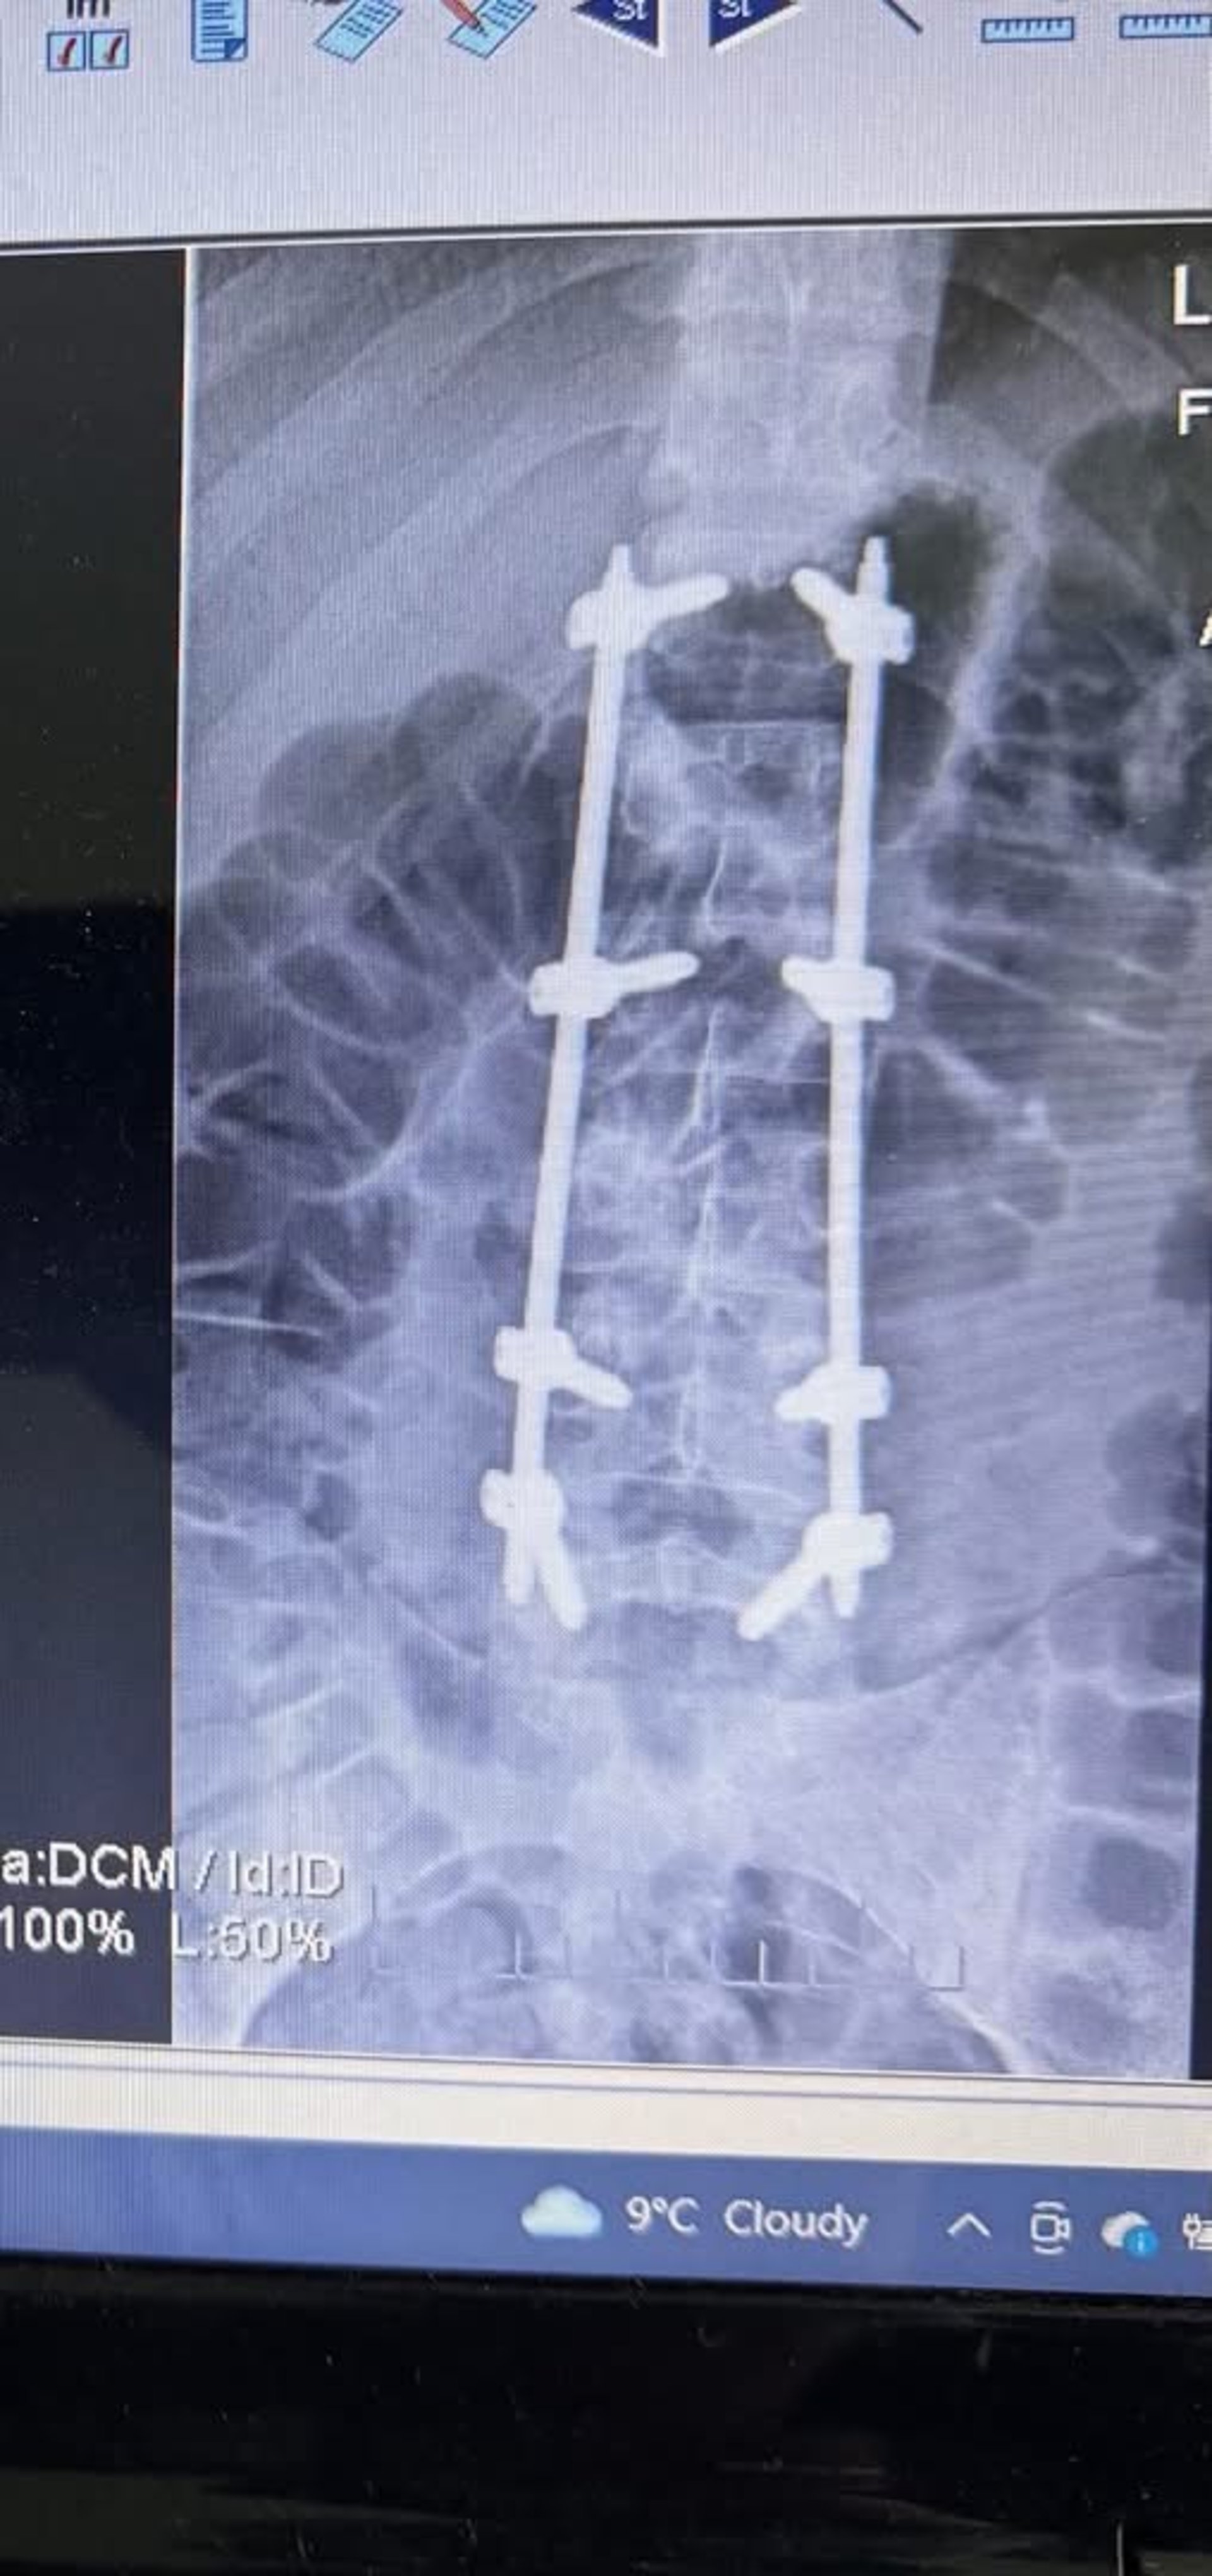

У Дрогобицькій міській лікарні №1 успішно прооперували 21-річного мотоцикліста, який отримав серйозні ушкодження внаслідок ДТП. Як повідомили у пресслужбі лікарні, медики діагностували у постраждалого закритий перелом двох хребців.

Травматологи вирішили застосувати сучасний малоінвазивний метод - транспедикулярну фіксацію хребта закритим шляхом. Під час операції лікарі встановили спеціальну конструкцію, яка стабілізувала хребет. Такий підхід дозволяє мінімізувати травматизацію тканин та пришвидшити одужання.